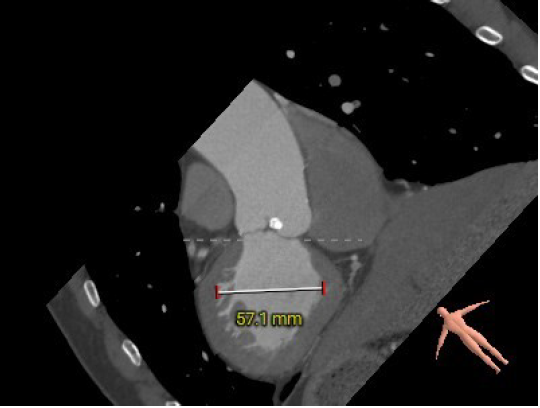

患者为78岁高龄男性,患者因反复胸闷急促1年,加重伴胸痛于5月慕名自行前来我院就诊。患者伴有肾功能异常、痛风、脑梗史,心功能III级。术前超声显示瓣环23mm,左房37mm,左室收缩末内径35mm。瓣上最大流速4.71m/s,峰值压差89mmHg,平均压差52mmHg,瓣口面积0.9cm²。诊断为主动脉瓣重度狭窄伴轻度关闭不全,三尖瓣轻度反流。

主动脉根部评估:

三叶式主动脉瓣,瓣环周长78.4mm,平均周长径24.9mm,左冠脉开口高度大于瓣叶长度,综合考虑冠脉风险低,LVOT周长径24.9mm,升主动脉直径30.8mm。

左冠高度17.5mm右冠高度22.6mm,右冠脉开口高度大于瓣叶长度,SOV瓦式窦:平均周长径38.2mm,术中仍球囊预扩须密切注意冠脉灌注,STJ周长径29.4mm。

瓣叶重度钙化伴增厚,钙化分布不均匀,HU596积分930mm²。

左室腔内径偏小,心室壁增厚明显。

主动脉弓角度与宽度可,心脏水平夹角53°,非横位心,外周血管内散见钙化灶,双侧入路血管内径良好,整体入路血管条件较好。